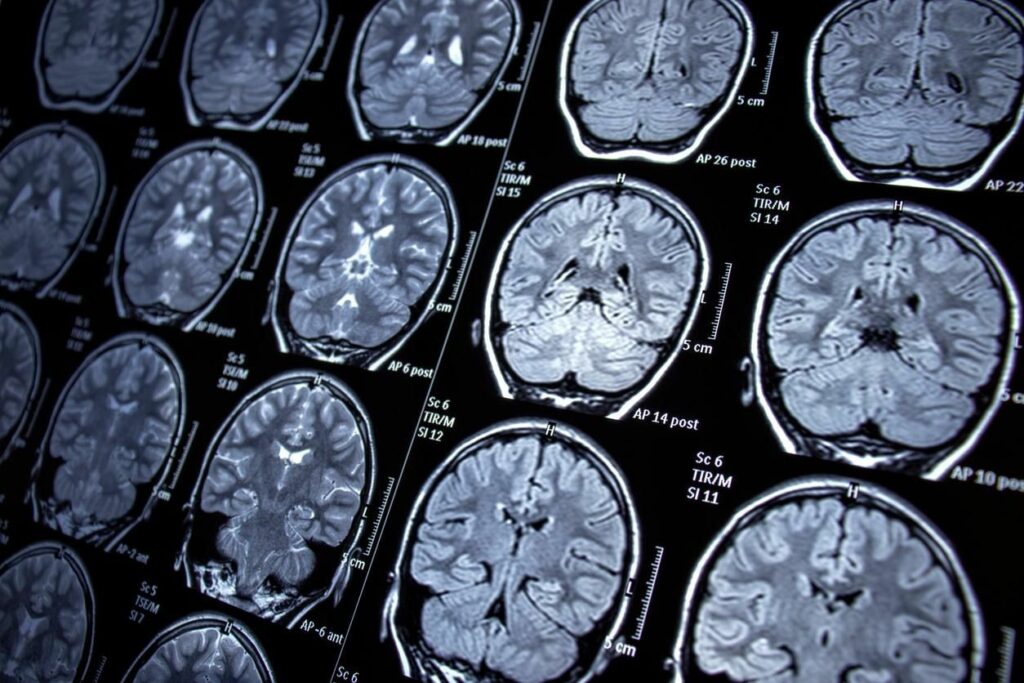

پژوهشگران در مطالعه خود از تصویربرداری پرتو مغناطیسی (MRI) برای افراد حاضر در «مطالعه‌ قلب فرامینگهام» (FHS) منفعت گیری کردند. این پژوهش برای بازدید طویل مدت بیماری‌های قبلی از سال ۱۹۴۸ روی ساکنین شهر فرامینگهام ایالت ماساچوست درحال انجام است. این مطالعه با قدمت ۷۵ سال، اکنون زیاد تر نسل دوم و سوم شراکتکنندگان مهم را بازدید می‌کند.

در مطالعه تازه، در فاصله سال‌های ۱۹۹۹ تا ۲۰۱۹ افراد متولد دهه ۳۰ تا ۷۰ میلادی حاضر در FHS تحت اسکن قرار گرفتند. در این پژوهش ۳۲۲۶ نفر مورد مطالعه قرار گرفتند که ۵۳ درصد آن‌ها زن و ۴۷ درصدشان مرد بودند. میانگین سنی این افراد در زمان MRI برابر ۵۷ سال می بود.

پژوهشگران MRI متولدین دهه ۳۰ و ۷۰ میلادی را با یکدیگر قیاس کردند. نتیجه قیاس‌ها‌، افزایش تدریجی اما مداوم چندین ساختار مغز می بود. برای مثال بازدید‌ها از افزایش مداوم حجم مغز (حجم داخل جمجمه‌ای) به‌صورت دهه به دهه خبر داد. حجم معز متولدین دهه ۳۰ میلادی به‌طور میانگین برابر ۱۲۳۴ میلی‌لیتر می بود، درحالی‌که حجم مغز متولدین دهه ۷۰ میلادی برابر ۱۳۲۱ میلی‌لیتر می بود که از تفاوت ۶.۶ درصدی حکایت دارد.

در این مطالعه سطح قشر مغز (اندازه‌گیری سطح مغز) افزایش بیشتری را نشان داد. متولدین دهه ۷۰ و ۳۰ به‌ترتیب سطح مغزی برابر ۲۱۰۴ سانتی‌متر‌مربع و ۲۰۵۶ سانتی‌مترمربع داشتند که از افزایش ۱۵ درصدی خبر می‌دهد. محققان این چنین فهمید شدند که ساختارهای مغزی همانند ماده سفید، ماده خاکستری و هیپوکامپ هم در متولدین دهه ۷۰ بزرگ‌تر از متولدین دهه ۳۰ می بود.